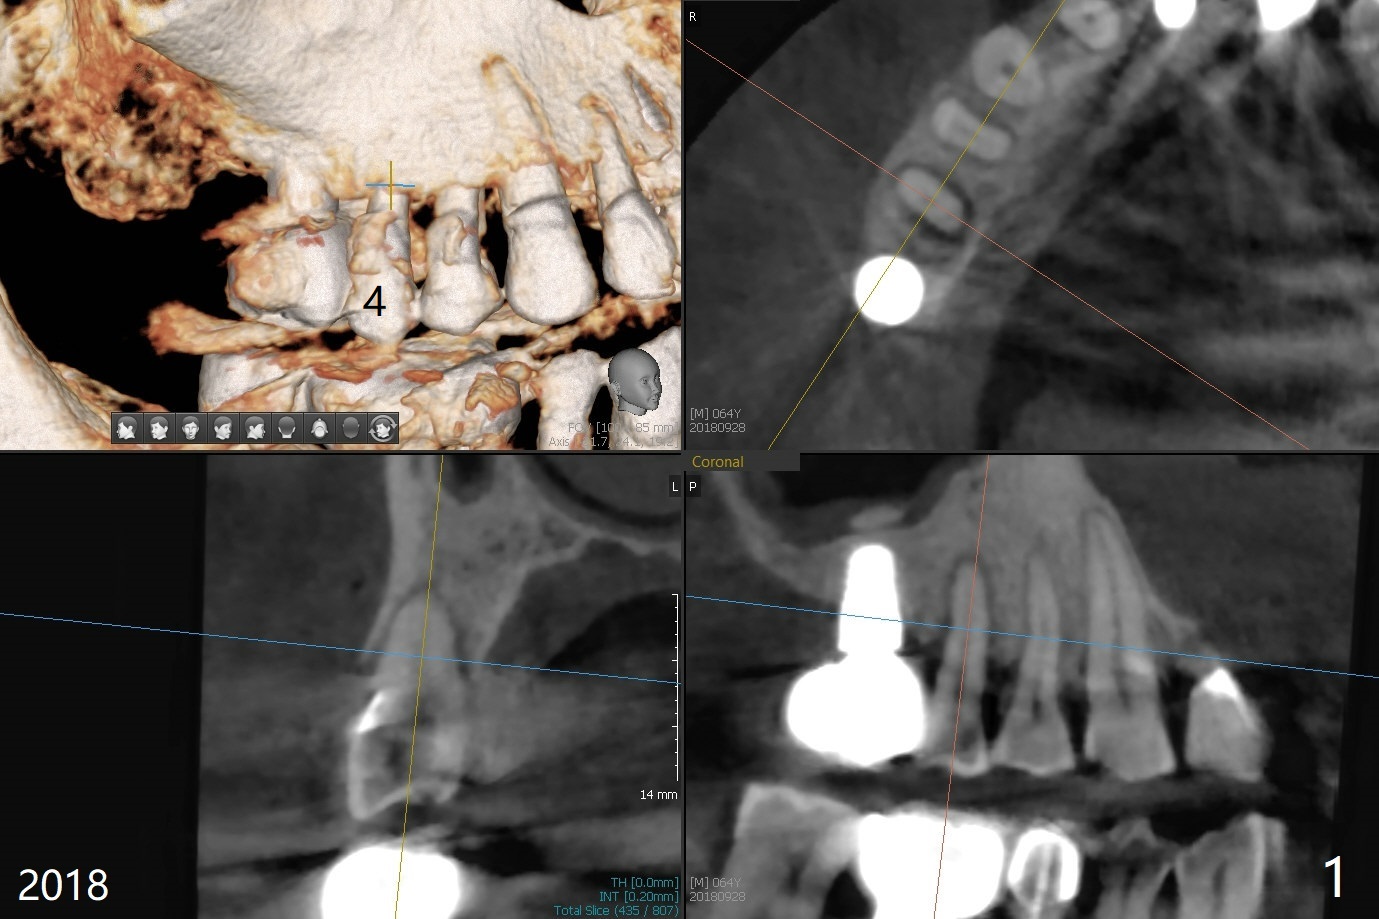

67岁男三年前CT显示4号牙牙周膜增宽(图一),最近咬到米粒中沙子突然松动(图二),要求退休前拔除种植(图三)。